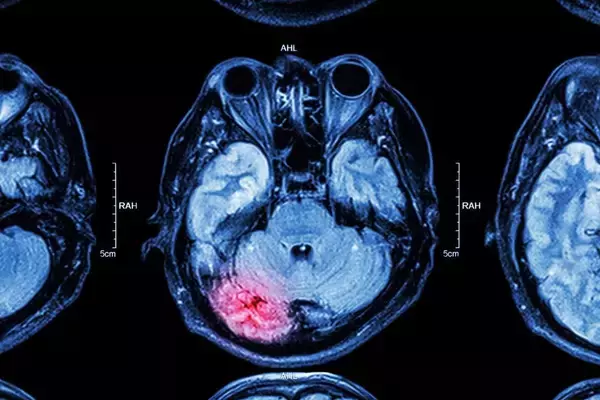

最初の結婚相手に浮気され、離婚。48歳で再婚した相手の家庭環境も複雑なものだった。50代女性が同居する高齢の義母は2度目の脳梗塞でほぼ全介助が必要な状態に。医師からは「回復の見込みはなく、自宅介護は無...